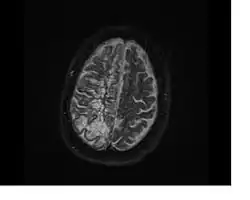

Perivascular spaces are most commonly located in the basal ganglia and white matter of the cerebrum, and along the optic tract.[13] The ideal method used to visualize perivascular spaces is T2-weighted MRI. The MR images of other neurological disorders can be similar to those of the dilated spaces. These disorders are:[7]

Perivascular spaces are distinguished on an MRI by several key features. The spaces appear as distinct round or oval entities with a signal intensity visually equivalent to that of cerebrospinal fluid in the subarachnoid space.[7][14][15] In addition, a perivascular space has no mass effect and is located along the blood vessel around which it forms.[14]